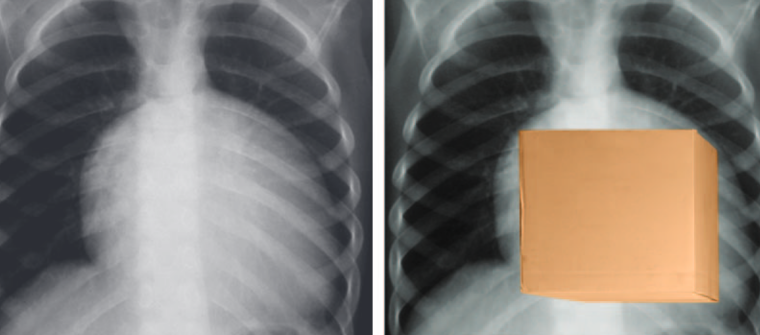

Anomalie d’Ebstein

- Déplacement inférieur de la valve tricuspide

- Dilatation massive de l’OD (signe du carton)

- VD “atrialisé”